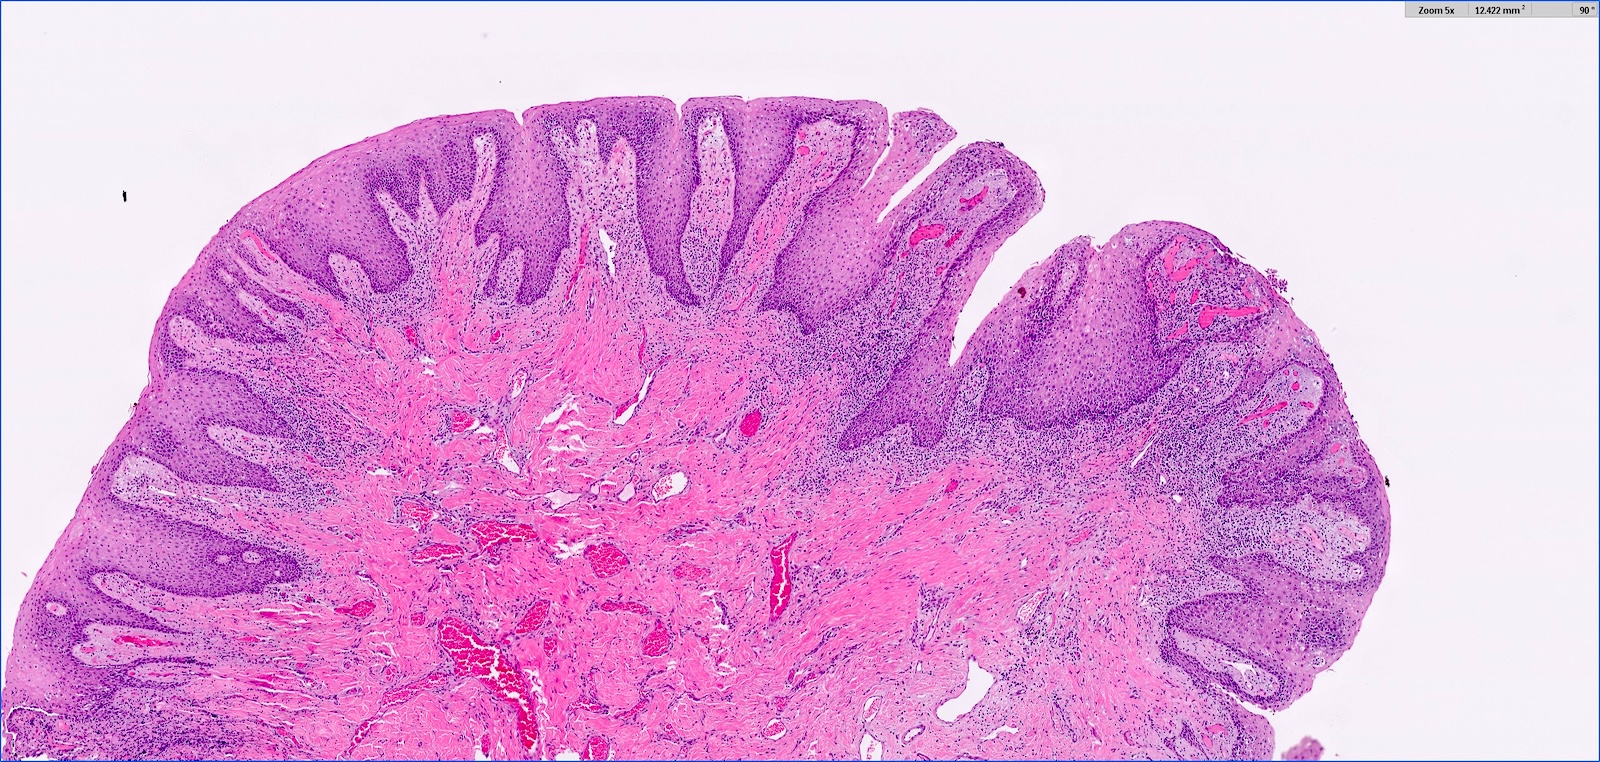

- Hyperplastic keratinized squamous mucosa overlying dense nodular connective tissue and variable inflammatory infiltrate (Acta Histochem 2016;118:451, Head Neck Pathol 2019;13:103)

- Underlying connective tissue is variably collagenized with scant bland spindled fibroblasts (Head Neck Pathol 2019;13:103)

- Pseudoepitheliomatous hyperplasia or secondary candidal colonization may be present